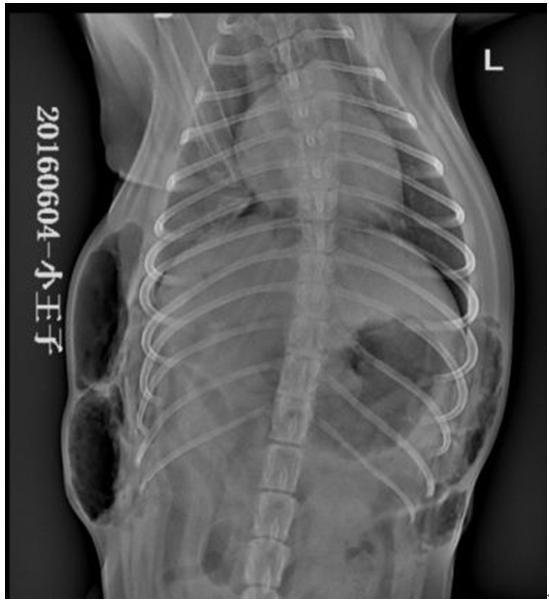

X线检查所示,右侧卧片可见,T9至L3之间背部皮下积气,肺脏萎缩,膈三角区密度降低,积气;仰卧位可见, T6至L3左侧胸部皮下气肿,右侧T8至L2右侧胸部皮下气肿,右侧膈角尖锐,密度降低,积气,提示胸壁透创并发气胸。